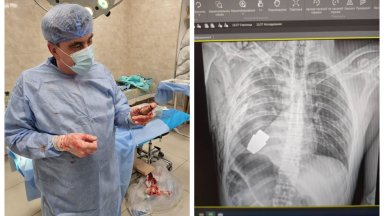

Военни лекари в Украйна са извадили взривателя на ръчна граната от гърдите

...... състоянието му е стабилно“, съобщава и Антон Геращенко, съветник към вътрешното министерство на Украйна. Говорителят на военномедицинските сили в страната уточнява, че войникът е на 28 години.

В разгара на руската агресия срещу Украйна военни лекари са

...... роден през 1994 г., сега е изпратен за рехабилитация, състоянието му е стабилно. Мисля, че този случай ще влезе в учебниците по медицина", казва тя.